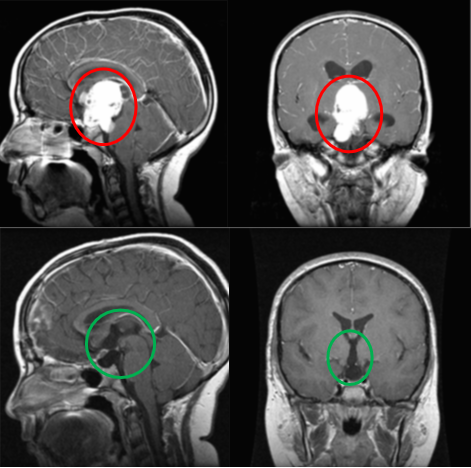

术前术后影像对比(红色术前,绿色术后)